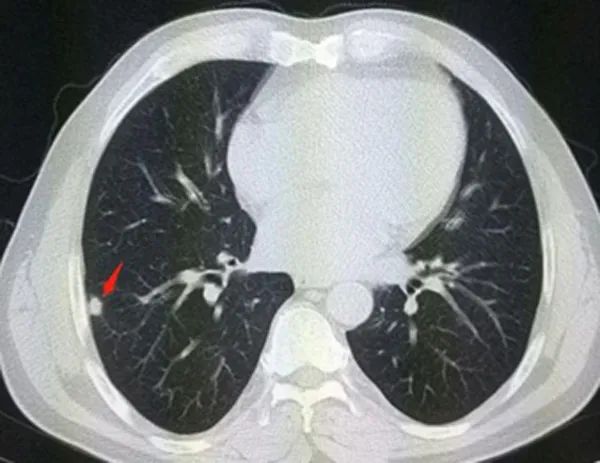

实性结节

实性肺结节:肺圆形或类圆形密度增高影,病变密度足以掩盖其中走行的血管和支气管影;